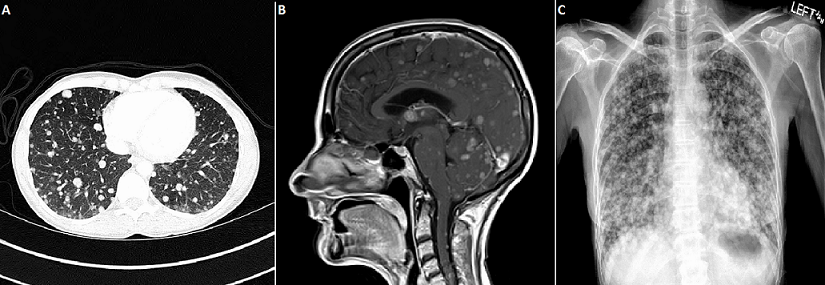

Extensive cerebral and extracerebral metastases from a large-cell neuroendocrine cervical carcinoma

A 43 year-old woman, gravida 2 para 2 with no regular medical care, presented for 3 months of pelvic pain and vaginal bleeding. Pelvic examination revealed an 8-cm necrotic cervical mass. Biopsy of the lesion demonstrated high-grade large-cell neuroendocrine carcinoma (LCNEC) of the cervix. CT with contrast of chest, abdomen and pelvis showed extensive pulmonary (A), hepatic and renal metastases (Stage IVB). She received palliative radiation, 6 cycles of etoposide and cisplatin and 1 cycle of bevacizumab. Seven months after diagnosis she developed intermittent headaches and expressive aphasia. MRI, pre-gadolinium and post-gadolinium, revealed numerous parenchymal and leptomeningeal contrast-enhancing lesions affecting brain and spinal cord (B). Chest X-ray re-demonstrated innumerable lung metastases (C). The patient decided to pursue hospice care and died 1 month later. Brain metastases from cervical cancer are exceedingly rare. However, brain metastases can occasionally occur from neuroendocrine cervical carcinomas, which account for up to 2% of all cervical cancers. LCNEC is an aggressive, poorly differentiated neoplasm with high mitotic rate, lymphovascular space involvement, and extensive necrosis. It metastasizes early. Due to the rarity of LCNEC, there are no randomized controlled trials evaluating therapies. Clinical guidelines suggest that treatment with surgical resection followed by platinum-and etoposide-based combination chemotherapy can improve survival in early stages. Still, LCNEC has poor prognosis. In a series of 62 patients, median overall survival for stage I, II, III, and IV LCNEC was 19, 17, 3 and 1.5 months, respectively.